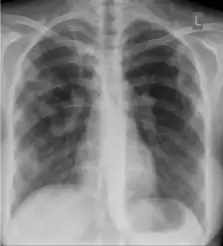

-

Dense homogenous opacity in right, middle and lower lobe of primary pulmonary TB. -